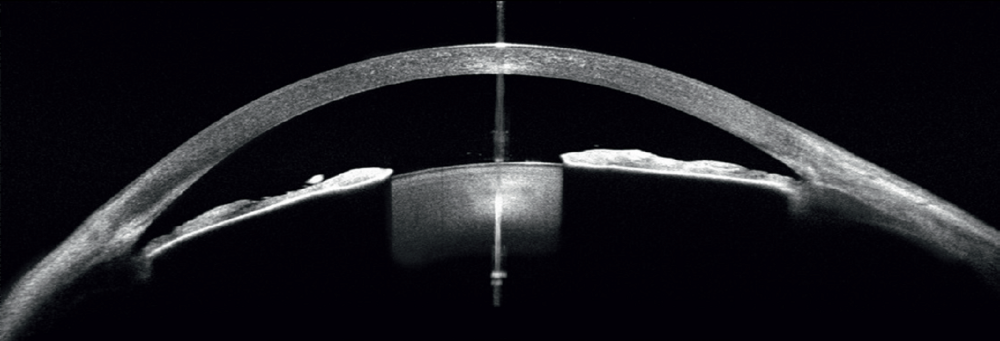

- Biométrie OCT : B-OCT® est une méthode innovante d'utilisation du dispositif OCT postérieur pour mesurer la structure oculaire le long de l'axe de l'œil. Un calculateur IOL est également disponible.